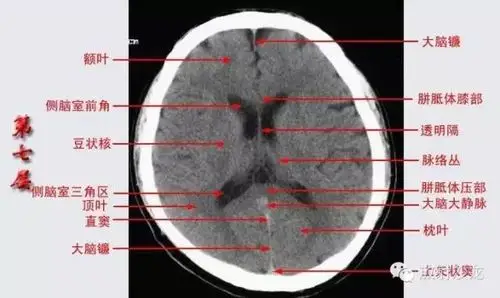

头颅ct断层解剖